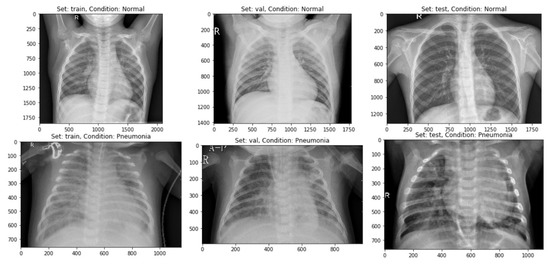

This depicts that there were 1583 images for the “Normal” class and 4274 images for class “Pneumonia”. This depicts that ~27% of the data had been represented through “Normal” class, whereas ~63% of the CXR images had “Pneumonia”. As the CXR images can be sensitive to slight changes in shearing, rotation, or zooming, data augmentation had been avoided in the CXR image dataset. Therefore, the data could not be undersampled or oversampled. The sample of images for each of the sets has been displayed below as in Figure 4.

Figure 4.

A sample of CXR images having both the classes separated into Train, Validation, and Test datasets.